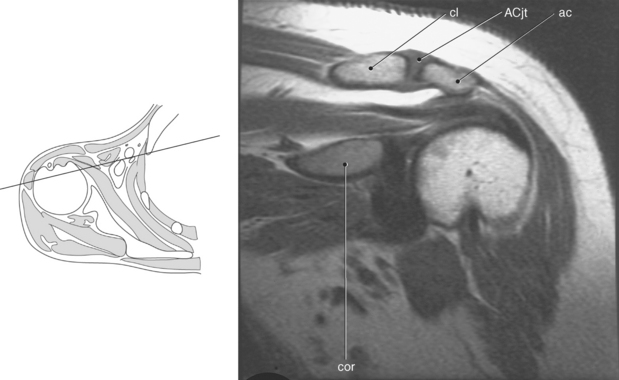

Figure 9.10 Sagittal oblique, T1-weighted MR scan of shoulder.

Key: cor, Coracoid process; cl, clavicle; sup, supraspinatus; ac, acromion; inf, infraspinatus; de, deltoid; tm, teres minor; gl, glenoid; sub, subscapularis; h, humerus; grt, greater tubercle; sc, scapula; glf, glenoid fossa; hh, humeral head.